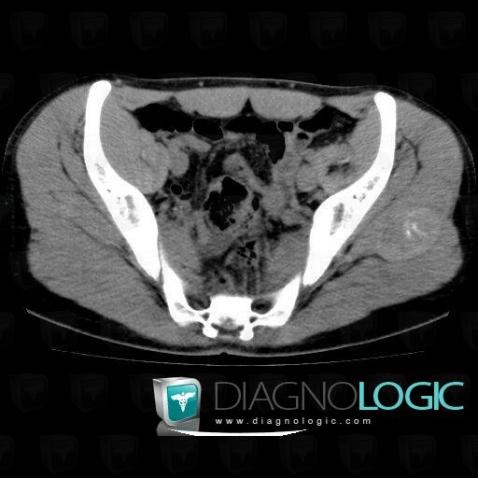

Hematoma, Other soft tissues/nerves - Pelvis, CT

Here is the specific information in the key image above:

- Diagnosis Hematoma, Location(s) Other soft tissues/nerves - Pelvis, with gamuts Soft tissue mass with calcification